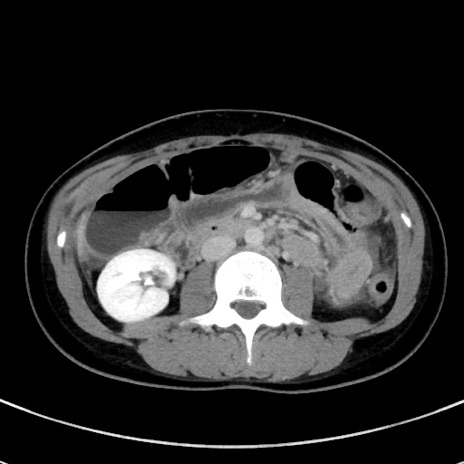

症例17(横断像)

【症例】20歳代女性

【主訴】嘔吐、下腹部痛

【現病歴】昨日夕食後に嘔吐し下腹部痛が出現。本日になっても嘔吐持続し改善しないため来院。

【身体所見】意識清明、BT 37.2℃、BP 108/67mmHg、腹部:平坦、やや硬、下腹部正中から右にかけて圧痛あり、反跳痛軽度あり、tapping pain(+)。

【データ】WBC 13600、CRP 14.94